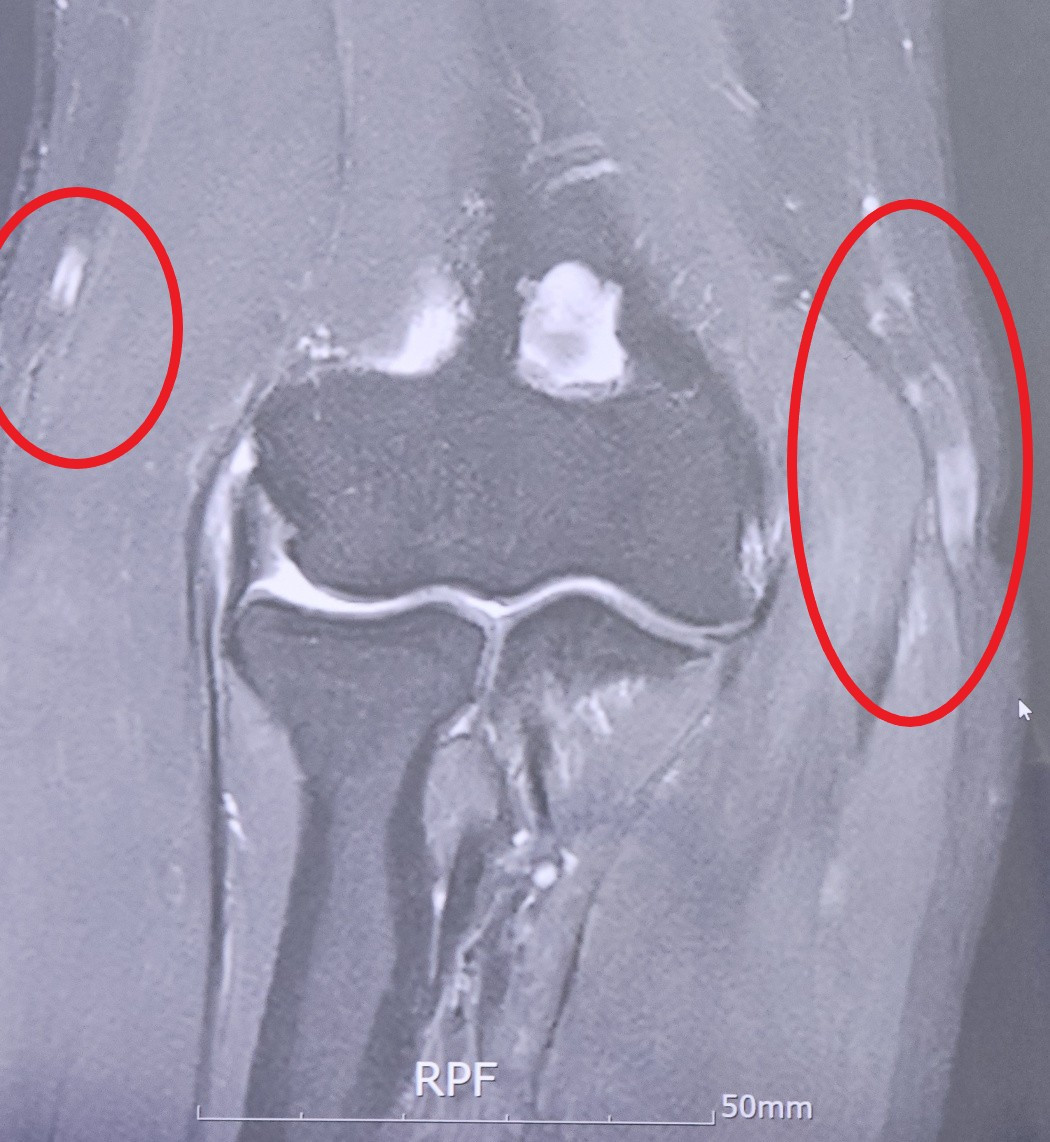

MRI를 찍어보니 속 시원히 알 수 있었다. 오른쪽 팔꿈치 안쪽 인대 끝 부분이 원래 붙어있어야 할 곳에서 떨어져 있었다. 바깥쪽 인대는 끝부분은 붙어있었지만 팔꿈치에서 손목 쪽 위치가 떨어져 있었다. 붙어있어야 할 곳에 붙어있지 않은 인대, 그리고 그걸 유발한 손상 부분이 통증의 원인으로 지목됐다. 이전에 다녔던 병원들에서는 문진과 촉진 결과를 바탕으로 진단을 내렸기 때문에 심각성을 잘 느끼지 못했다. 그런데 MRI를 찍어보니 심각한 상황이라는 걸 알 수 있었다.

KakaoTalk_20250526_104610542_01.jpg 빨간색 타원 안이 손상된 힘줄. MRI 사진. ©선정수